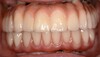

Vue intra-orales des deux bridges. Noter les belles papilles au maxillaire antérieur et le retrait de la mandibule vers l’arrière corrigé par le montage des dents prothétiques.

Vue du sourire gauche

Vue du sourire droit.

Vue du sourire de face. La patiente a retrouvé son sourire et sa personnalité.